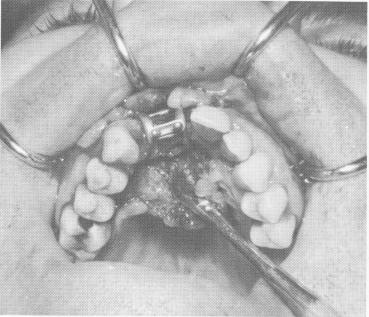

Fig. 12-92. The implant was fitted over the exposed bone.